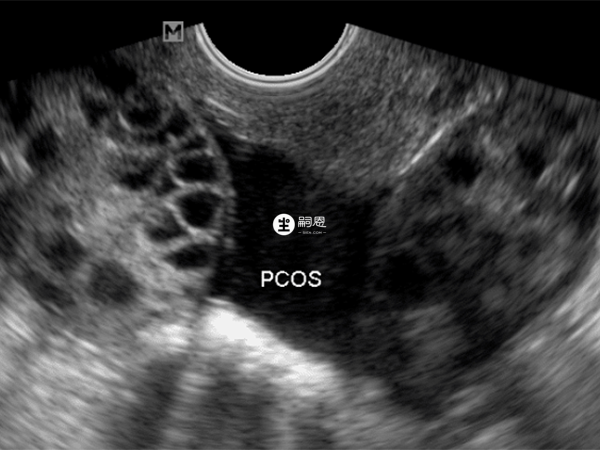

多囊卵巢综合征是一种生殖内分泌代谢性疾病,患者体内激素水平会较高,这就会导致卵巢内的卵泡发育异常,无法自然生长大发生排卵,就会导致不孕的情况发生。不过多囊卵巢治疗后怀孕几率还是较大的,治疗方法主要就是促排卵或辅助生殖助孕,下面就为大家介绍多囊卵巢助孕做人工授精和试管移植的成功率: